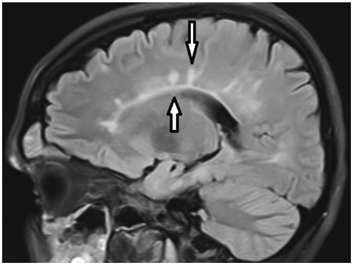

A 27-year-old female presented a one-year history of psychiatric and cognitive symptoms and headache. Then the vision acceded, but there was no hearing dysfunction. Cerebro-spinal fluid and hematology tests were within the normal range. MRI showed “snowball” and “icicle” lesions in the CC (Figure 2). There were BRAO on fluorescent angiography. Long-term high-dose dexamethasone therapy leads to clinical improvement.

The hallmark callosal lesion in SS is the “snowball” lesion as the appearance resembles a snowball on sagittal T2 and FLAIR sequences (as you can see in our patients' MRI). These likely pathognomonic lesions of SS are small (3–7 mm) and multifocal, involving the central fibers of the CC with relative sparing of the periphery.1 They represent microinfarctions due to occlusion of small precapillary arterioles consistent with the microvascular blood supply of the CC. The roof of the CC is more commonly affected, with microinfarcts taking on “icicle” and “spoke” configurations (Figure 3). It is important to note that MRI lesions in SS can disappear in comparison to MS lesions (Figure 5).